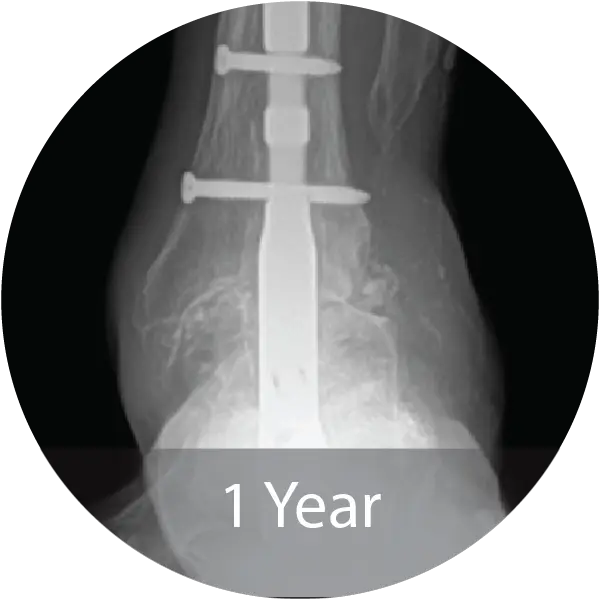

Case of 64-year-old female with hindfoot arthritis treated with tibiotalocalcaneal arthrodesis and intramedullary nailing using InduceXT®. Reported solid osseous consolidation with no postoperative complications, pain-free ambulation, and full return to activities.